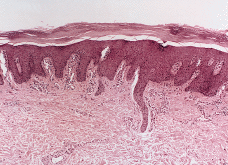

FIG. 2.--Biopsia cutánea tomada en el primer año de vida. Se aprecia acantosis psoriasiforme con atrofia de la granulosa y una córnea engrosada en la que alternan capas horizontales ortoqueratosis (azules) y paraqueratósicas (rojas). Leve infiltrado linfocitario en algunas papilas.

FIG. 5.--Biopsia cutánea tomada a los 17 años de edad. Existe hiperqueratosis ortoqueratósica compacta, atrofia de la granulosa con áreas de paraqueratosis, acantosis psoriasiforme e hiperplasia vascular dérmica superficial.